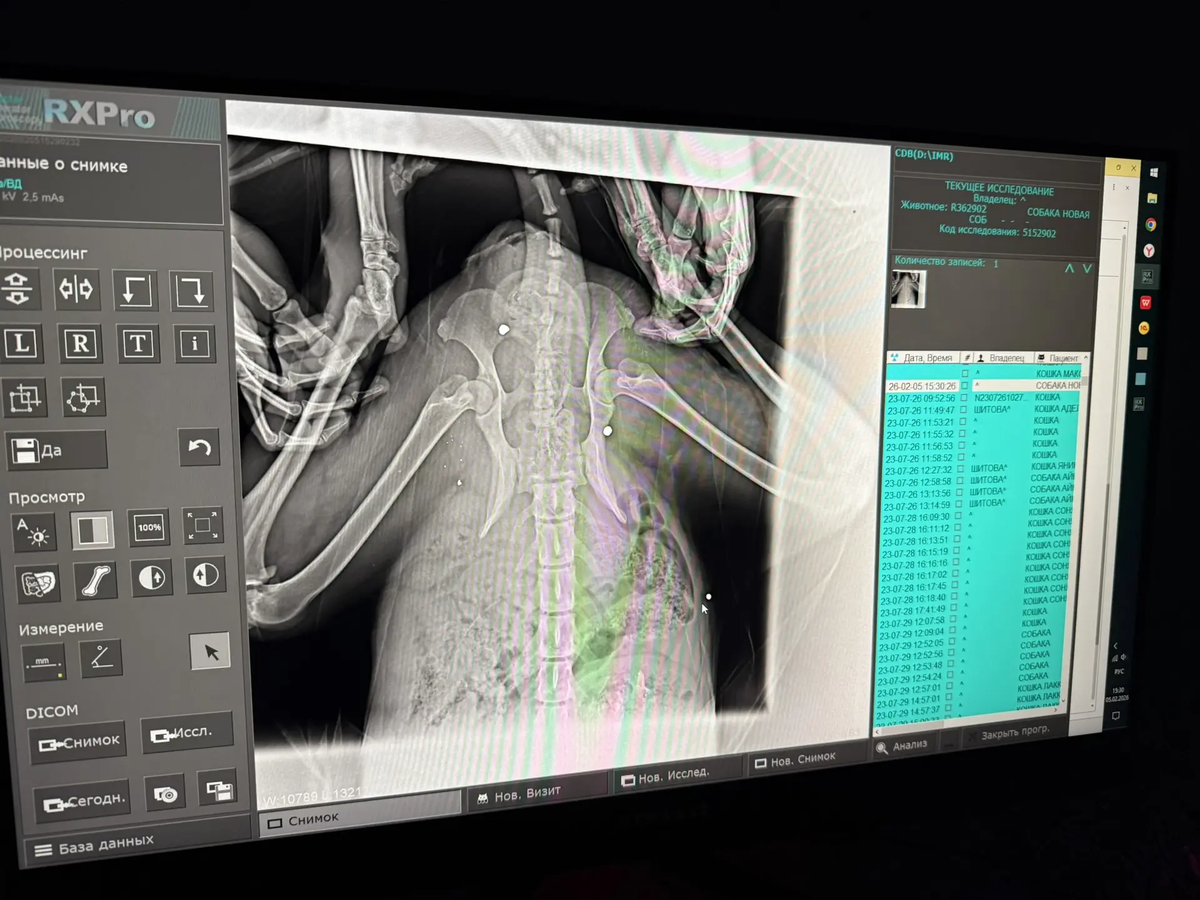

У собачки сохранена чувствительность в лапках, но сами задние лапы уже стёрты и в ранах. Мы сделали рентген (оставались денежки с оплаты аренды) и были в шоке. В очередной раз перед нами собака, в которую стреляли ИЗ ДРОБИ! Таз, брюшко — ВСЁ В ПУЛЯХ! Перелом таза…

А ещё, похоже, ПНЕВМОНИЯ! Нужен кардиолог, травматолог. Нужно сдать кровь обязательно — общий и биохимию, ПЦР. Также у собачки полный желудок КОСТЕЙ.